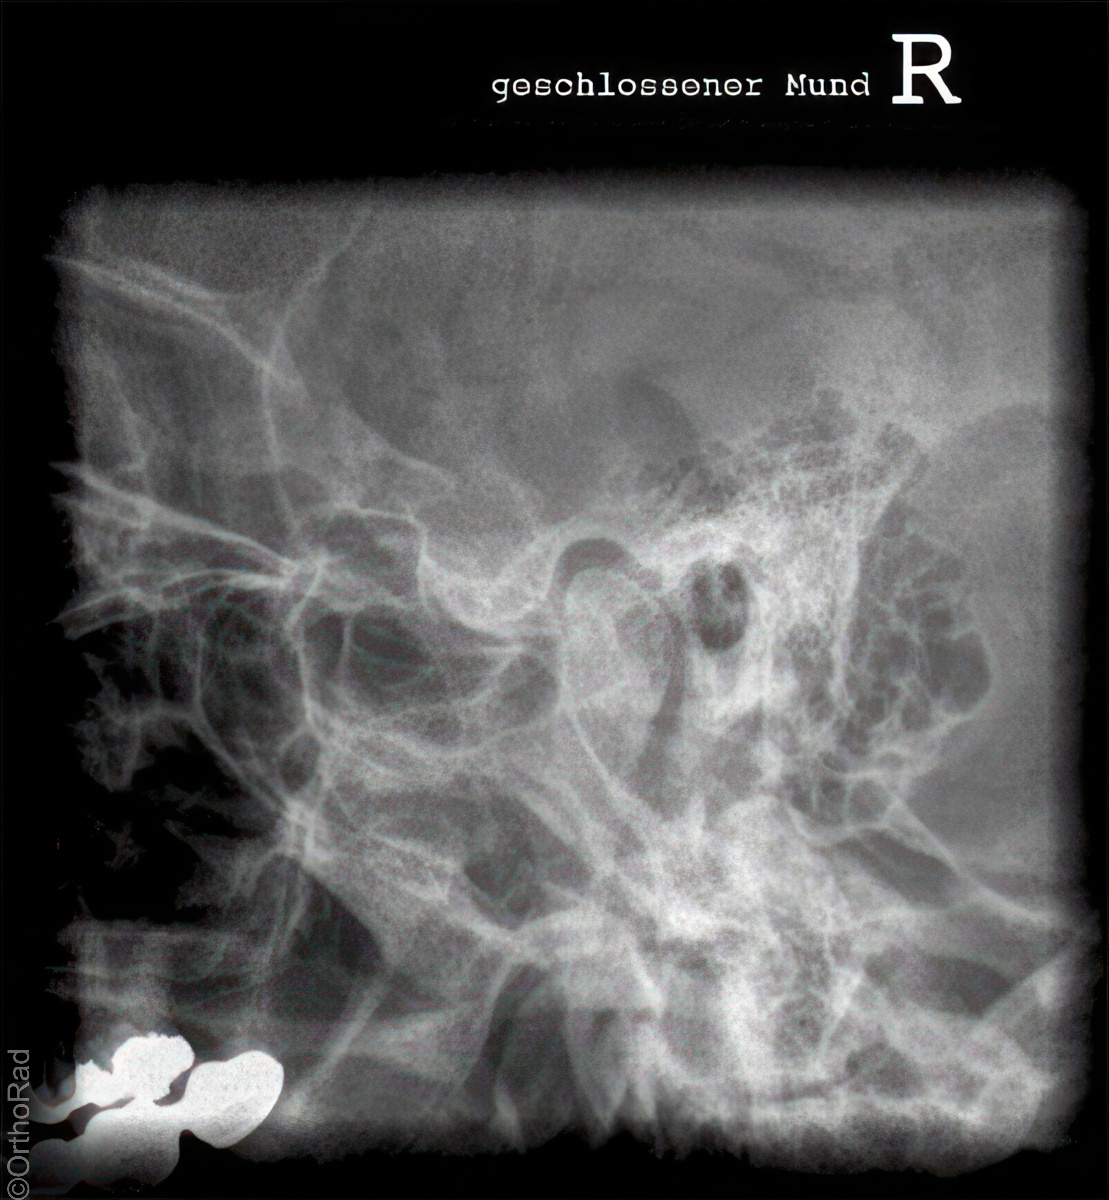

Unterkiefer nach Clementschitsch

Es wurden keine Bilder gefunden.

Technik

• FDA: 1,15 m

• Ausgangsformat: 18/24 hoch

• mit Raster

• Röhrenkippung: 15° caudo-cranial

Lagerung

sitzt aufrecht und gerade mit dem Gesicht zum Stativ

Kopf gerade

Kinn stark anziehen lassen

Stirn dem Stativ anliegt

Mund maximal öffnen

Zentralstrahl

Im Winkel von mindestens 15° caudo-cranial okzipitomental. Längsstrahl verläuft durch die Medianebene. Querstrahl unterhalb des Occiputs auf Nasenwurzel. Achtung! Bei Röhrenkippung auf Zentrierung achten.

Anmerkung

Vollständige Darstellung des Unterkiefers und gute Beurteilung der Kiefergelenke. Bei Kiefergelenk Fragestellung:

1. Aufnahme mit geöffneten Mund

2. Aufnahme mit geschlossenem Mund

Qualitätskriterien

Übersichtliche Darstellung des gesamten Unterkiefers mit seitengleich gut einsehbaren Kiefergelenken